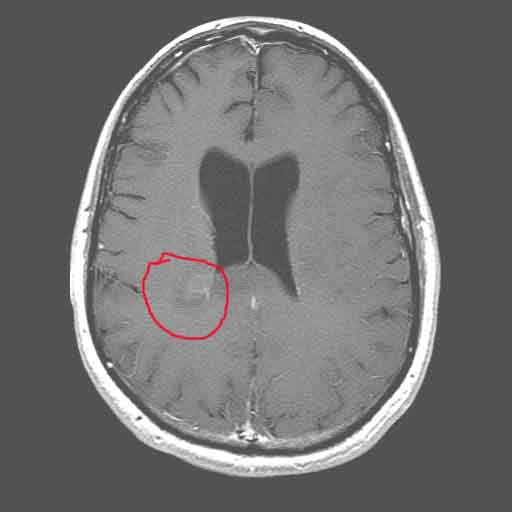

As we have known since January, my tumor is regrowing.  I had a short break where the Temodar seemed to be making some difference.  But, even the Temodar seems to be failing now.  I got an MRI last week showing a new mass deep in the white matter of the parietal lobe.  I have known for some time that I have been getting worse and worse.  I asked Abi “What’s different today than yesterday?”  And she said “Now we have radiological confirmation that the tumor is regrowing.”  And the kicker is, that there is no additional treatment for this type of tumor – in either Western or Eastern medicine.  Well, ok, there are treatments I could try, with known severe side effects, and very minimal effectiveness.  Maybe adding 6 or 9 months to my life, if they work.